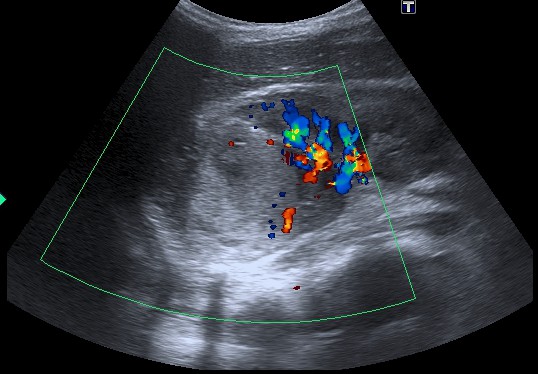

- Es útil el Doppler para valorar afectación de la vena cava inferior por trombo tumoral.